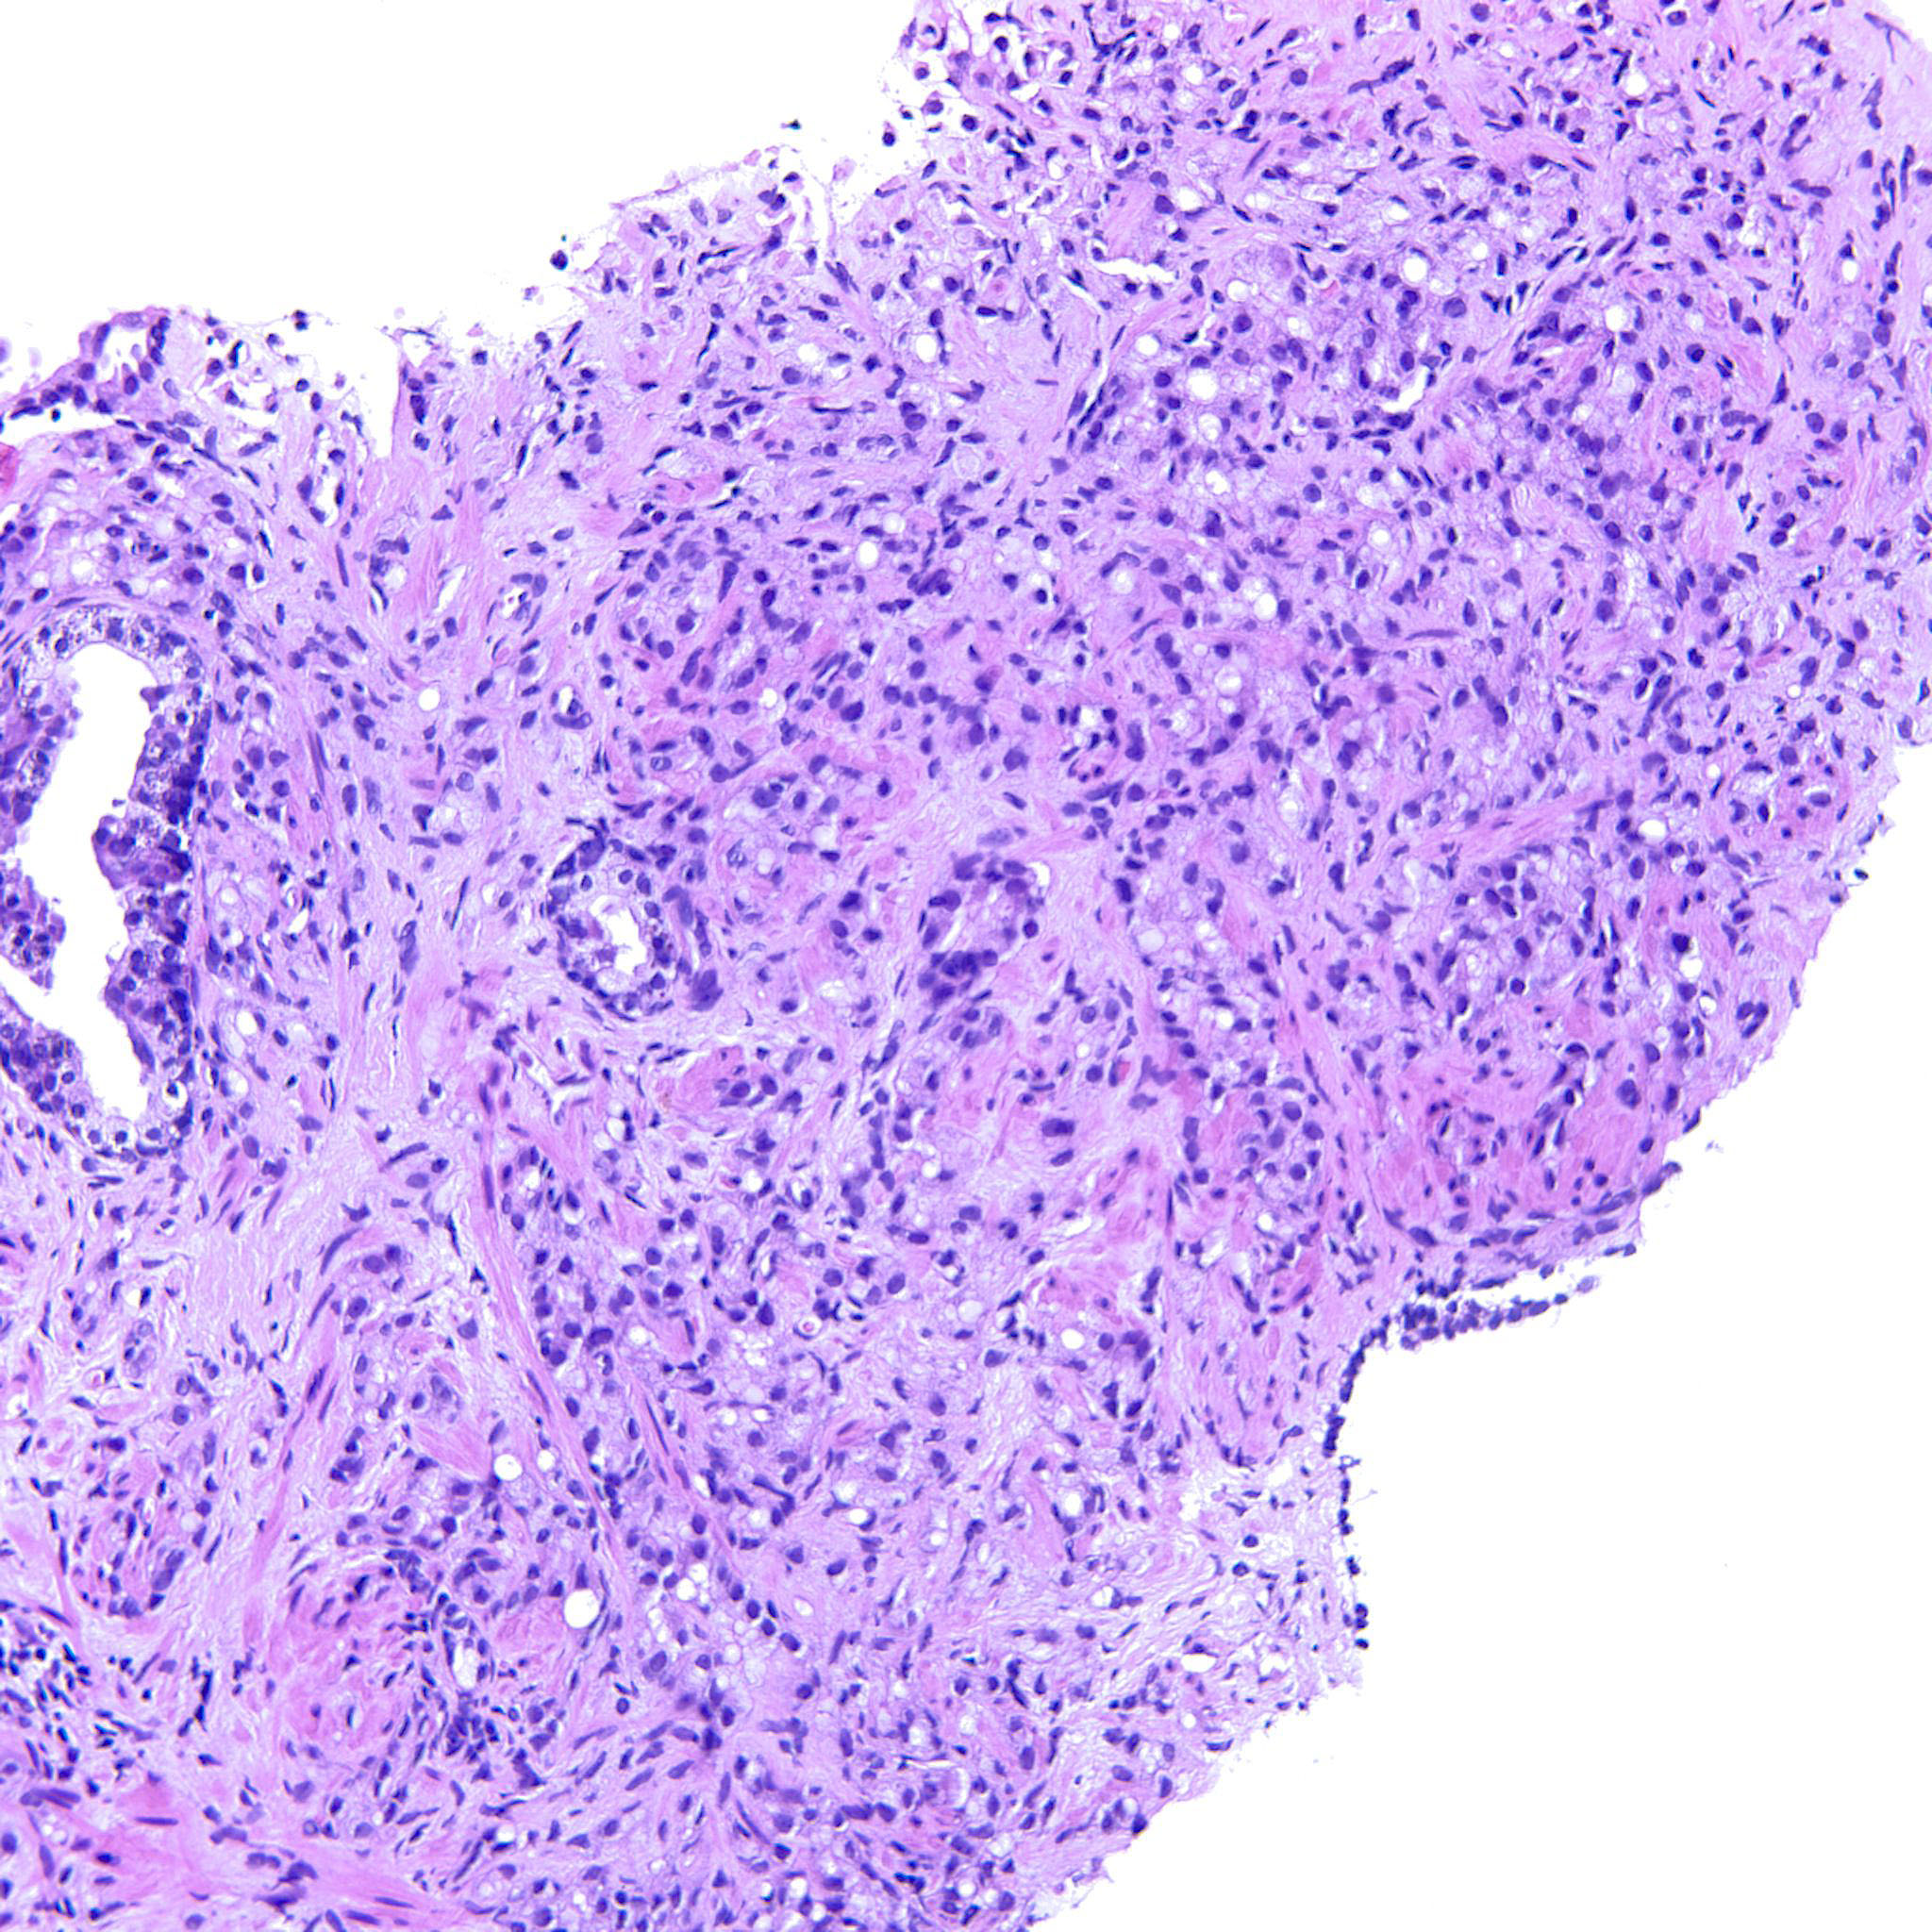

Prostate cancer grading

Case ID: 744